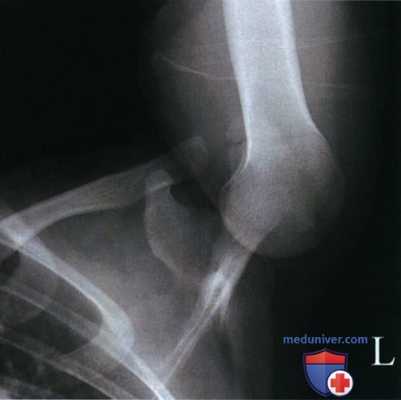

• Клювовидный отросток накладывается на латеральный отдел ключицы (рис. 3)

• Заднелатеральная поверхность головки плечевой кости видна в профиль с латеральной стороны; если есть, то виден дефект Хилла-Сакса (рис. 4 и 5)

• Большой и малый бугорки видны частично в профиль соответственно с латеральной и медиальной сторон (рис. 6 и 7)

• Клювовидный отросток находится в центре экспозиционного поля

• В экспозиционное поле входят головка плечевой кости, клювовидный отросток, латеральный отдел ключицы, суставная впадина лопатки и верхняя треть тела лопатки.

РИСУНОК 3 Рентгенограмма плечевого сустава в аксиальной ПЗ проекции (по Страйкеру). Верх срединной коронарной плоскости был наклонен вперед, либо ЦП был наклонен кра-ниально менее чем на 10°. РИСУНОК 4 Рентгенограмма плечевого сустава в аксиальной ПЗ проекции (по Страйкеру). Плечевая кость была отведена дальше вертикального положения. РИСУНОК 5 Рентгенограмма плечевого сустава в аксиальной ПЗ проекции (по Страйкеру). Плечевая кость не была доведена до вертикального положения. РИСУНОК 6 Рентгенограмма плечевого сустава в аксиальной ПЗ проекции (по Страйкеру). Визуализируется крупный дефект Хилла-Сакса. Дистальный отдел плечевой кости был наклонен латерально. РИСУНОК 7 Рентгенограмма плечевого сустава в аксиальной ПЗ проекции (по Страйкеру). Дистальный отдел плечевой кости был наклонен медиально.

в) Наклон верха срединной коронарной плоскости вперед или избыточный каудальный наклон ЦЛ. Если при рентгенографии плечевого сустава в аксиальной ПЗ проекции верх срединной коронарной плоскости наклонен вперед, или ЦЛ наклонен краниально меньше, чем на 10°, то клювовидный отросток будет визуализироваться ниже ключицы. При этом заднелатеральная поверхность головки плечевой кости будет закрыта, поскольку ЦЛ неправильно ориентирован относительно последней. Кроме того, диафиз плечевой кости подвергнется большему проекционному укорочению (рис. 3).

г) Отведение плечевой кости дальше вертикального положения. Если при рентгенографии плечевого сустава в аксиальной ПЗ проекции ЦЛ наклонен правильно, но плечевая кость отведена дальше вертикального положения, в полученной рентгенограмме заднелатеральная поверхность головки плечевой кости будет закрыта, а диафиз плечевой кости будет проекционно укорочен (рис. 4).

д) Отведение плечевой кости, не достигающее вертикального положения. Если при рентгенографии плечевого сустава в аксиальной ПЗ проекции ЦЛ наклонен правильно, но плечевая кость отведена, но не доведена до вертикального положения, на рентгенограмме заднелатеральная поверхность головки плечевой кости будет закрыта, а диафиз плечевой кости будет проекционно укорочен (рис. 5).